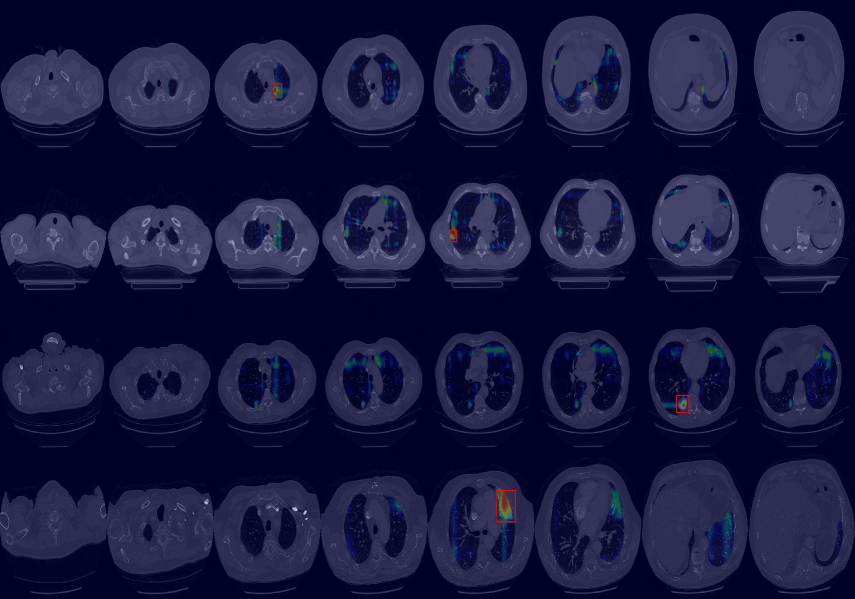

Finally, we evaluated the 3D abnormal (lesion) localization performance of the proposed VMPR-UAD. Of the 63 cancer cases in the MSD dataset with ground-truth annotations available, we excluded two cases (cases 38 and 96) of incorrect annotation or showing other diseases. We calculated whether the cancer area predicted by VMPR-UAD (binarized at a certain high-probability threshold) overlapped with the annotated cancer area. As a result, 57 of the 61 cases showed overlapping, demonstrating that VMPR-UAD can localize 3D lung anomalies (cancer in this case) with an accuracy of 93. Some localization examples in 3D data are shown in Fig. L. The red points in Fig. L(b) show the 3D cancer locations that the proposed method estimates with the highest confidence (i.e., location of highest pixel value in the 3D anomaly map). The red points in Fig. L(a) show the ground-truth cancer location. The ground truth and prediction shown in Fig. L confirm that VMPR-UAD correctly finds the lung anomaly 3D region. More detailed visualization results are available in the Supplementary Material. The prediction consistency can also be observed in 2D slices, as shown in Fig. M, where our anomaly localization map indicates correct cancer regions. Hence, the proposed VMPR-UAD can automatically localize or segment lesions without requiring any lesion information (i.e., using only CT slices from healthy subjects) for training.